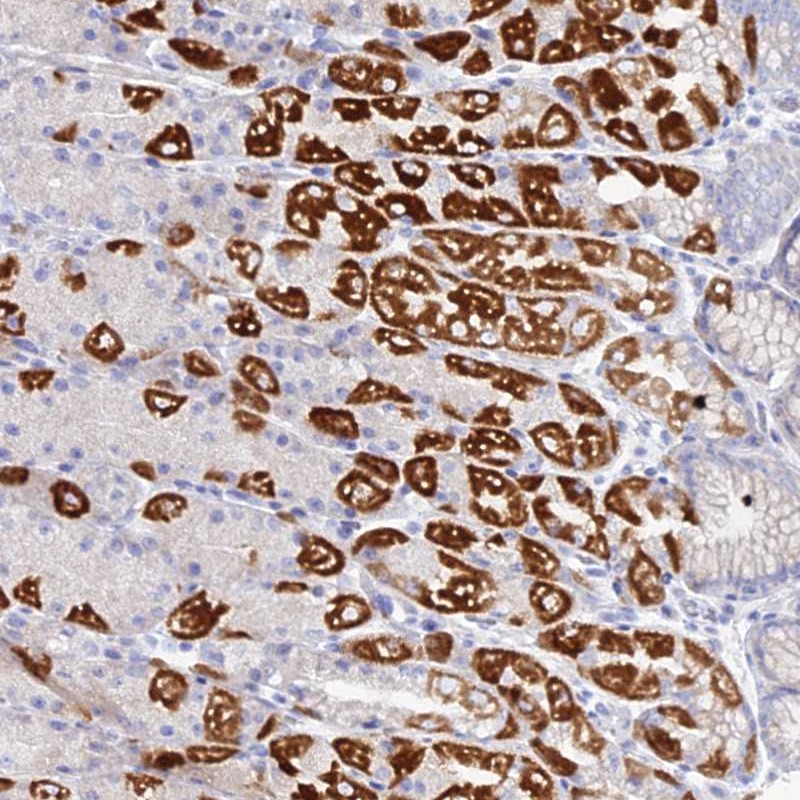

Immunohistochemical staining of human stomach, lower shows strong cytoplasmic positivity in parietal cells.